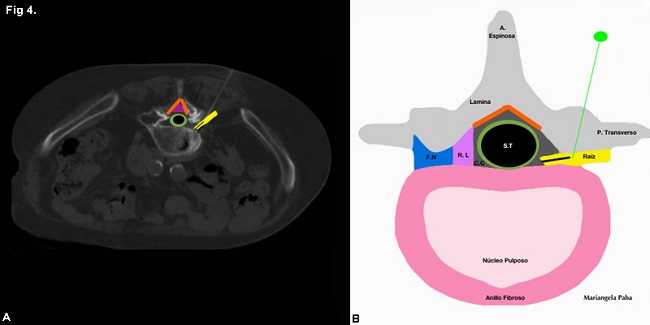

En total se estudiaron 46 pacientes, 34 mujeres (73,9%) y 12 hombres (26%) con una edad media de 67 años +/- 11,7 años (rango 33 a 89 años). En 27 (58%) de ellos se realizó bloqueo epidural (►Fig. 3) y en 19 (41%) bloqueo radicular (►Fig. 4) (►Gráfico 1).

Se utilizó iodopovidona para realizar la asepsia y se aplicó anestesia local con lidocaína al 2% para disminuir las molestias causadas por el procedimiento. Se introdujo una aguja espinal 21 G hasta el lugar afectado fuera radicular o epidural(►Fig. 1). Una forma de asegurar que se alcanzó la zona indicada en el caso de los bloqueos radiculares fue la reproducción del dolor referido por el paciente durante el interrogatorio, lo que se interpretó como contactando en el nervio comprometido (►Fig. 2). En bloqueos epidurales previo a la aplicación del medicamento, se inyectó 1 cm3 de aire para confirmar que la aguja se encontraba en el espacio correcto. En todos los casos se inyectó una solución compuesta de 30 mg de triamcinolona y 1,5 mg de clorhidrato de bupivacaina.